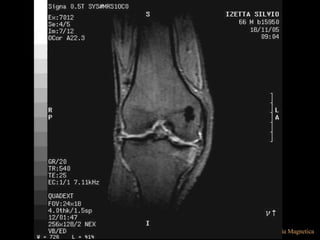

*STIR (SHORT TIME INVERSION RECOVERY)

• TI= CORTO PARA SATURAR LA GRASA,

• Útil para evaluar y diferenciar un componente

liquido de grasa

*STIR (SHORT TIMEINVERSION RECOVERY) • TI= CORTO PARA SATURAR LA GRASA, • Útil para evaluar y diferenciar un componente liquido de grasa